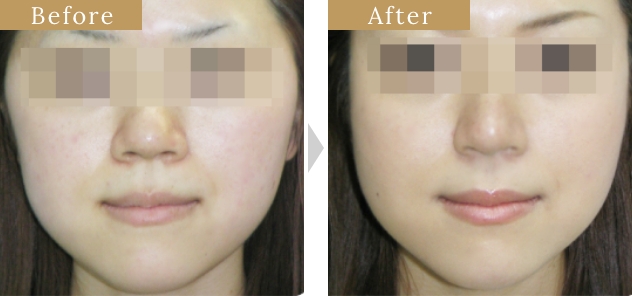

症例